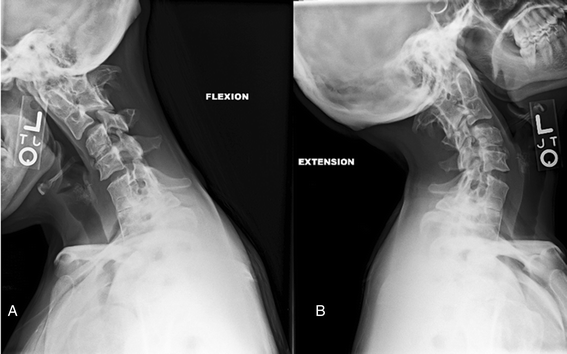

The authors analyzed the functional significance of anterior and posterior degenerative spondylolisthesis (anterolisthesis and retrolisthesis) of the cervical spine to elucidate its role in the development of cervical spondylotic myelopathy (CSM) in the elderly.

Partial retrolisthesis: One vertebra moves backwards either to a spinal segment below or above. Stairstepped retrolisthesis: One vertebra moves backwards to the body of a spinal segment located above, but ahead of the one below. Retrolistheses are typically found in the cervical spine (shoulder and neck region),...

Launching the subaxial external body part spine is self-possessed of c3 direct c7 vertebrae. The high vertebral body is displaced backwards relational to the vertebrae below.